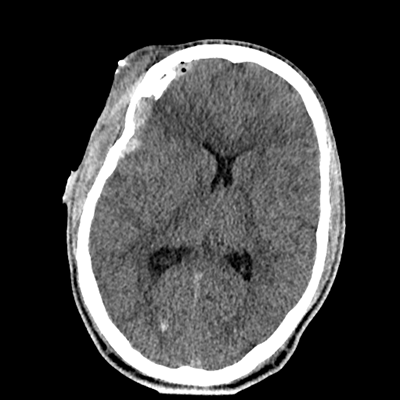

Initial vitals are notable for BP 111/67, HR 119, SpO2 100%, T 37.8C. She undergoes a whole-body CT scan. Trauma surgery also evaluates her. She has a zygomaticomaxillary complex fracture, comminuted fracture of her humerus, and fractures of ribs 2-6. Her non-contrast head CT is shown below. Plastic surgery evaluates her and recommends non-emergent operative repair of her facial fracture.

The patient has sustained multicompartmental hemorrhages—small amounts in the parenchymal, subarachnoid (mainly right frontal), subdural (right frontal, anterior temporal in particular), and intraventricular (layering in the right occipital horn) spaces. It’s a more subtle finding, but you can also see that the right hemispheric convexity has less sulcation, suggestive of cerebral edema on that side. There’s the right frontal contusion with hemorrhage there. There are also two small IPHs, in the right thalamus and left internal capsule. What do these represent? Likely diffuse axonal injury (DAI).